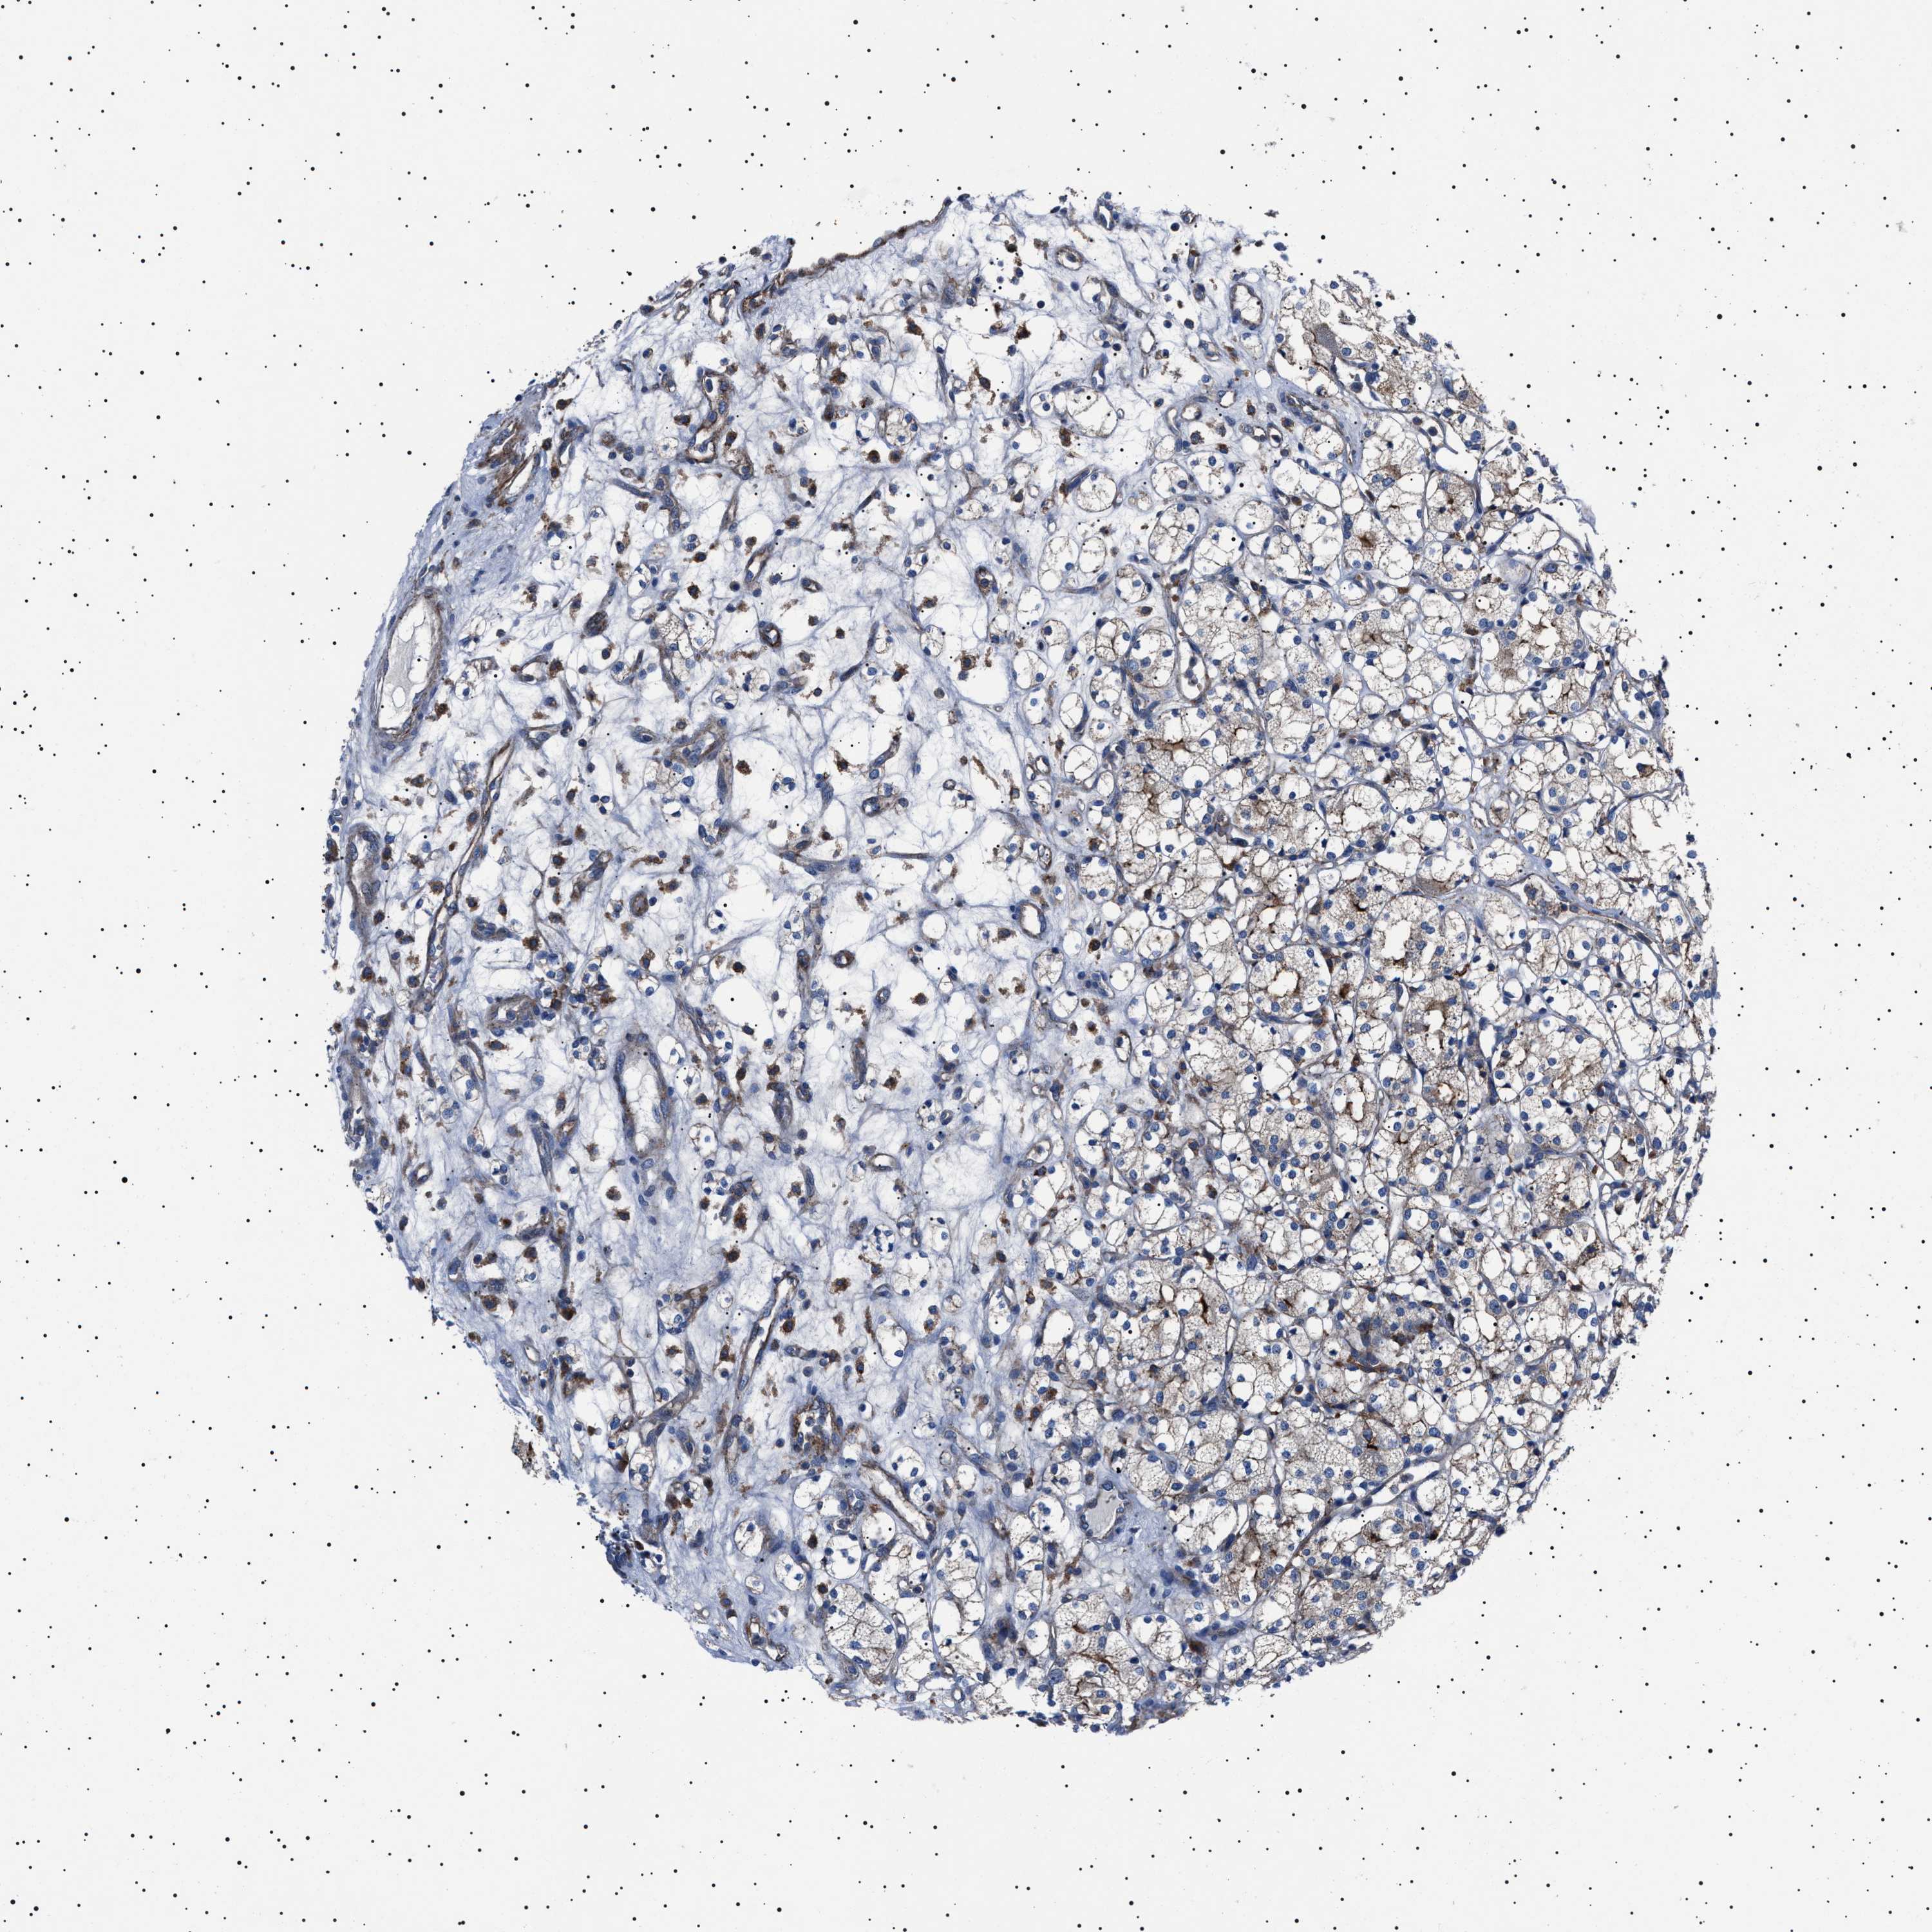

KIDNEY RENAL PAPILLARY CELL CARCINOMA (TCGA) - Interactive survival scatter ploti

The Survival Scatter plot shows the clinical status (i.e. dead or alive) for all individuals in the patient cohort, based on the same data that underlies the corresponding Kaplan-Meier plots. Patients that are alive at last time for follow-up are shown in blue and patients who have died during the study are shown in red.

The x-axis shows the expression levels (FPKM) of the investigated gene in the tumor tissue at the time of diagnosis. The y-axis shows the follow-up time after diagnosis (years). Both axes are complimented with kernel density curves demonstrating the data density over the axes. The top density plot shows the expression levels (FPKM) distribution among dead (red) and alive patients (blue). The right density plot shows the data density of the survived years of dead patients with high and low expression levels respectively, stratified using the cutoff indicated by the vertical dashed line through the Survival Scatter plot. This cutoff is automatically defined based on the FPKM cutoff that minimizes the p-score. The cutoff can be changed by dragging the vertical line or by entering a cutoff value in the square labeled "Current cut-off".

Under the Survival Scatter plot the p-score landscape (black curve; left axis) is shown together with dead median separation (red curve; right axis). Dead median separation is the difference in median mRNA expression between patients who have died with high and low expression, respectively. It is calculated as follows: median FPKM expression of dead patients with high expression - median FPKM expression of dead patients with low expression. This is intended to aid the user in visually exploring custom cutoffs and the associated p-scores and dead median separation.

Individual patient data is displayed and can be filtered by clicking on one or more of the category buttons on the top of the page. Categories describing expression level and patient information include: high, low, alive, dead, female, male and tumor stages. The scale of the x-axis can be toggled between linear and log-scale by clicking on the "x log" button. Mouse-over function shows TCGA ID, patient information and mRNA expression (FPKM) for each patient.

& Survival analysisi

Kaplan-Meier plots summarize results from analysis of correlation between mRNA expression level and patient survival. Patients were divided based on level of expression into one of the two groups "low" (under cut off) or "high" (over cut off). X-axis shows time for survival (years) and y-axis shows the probability of survival, where 1.0 corresponds to 100 percent.

NEU1 is not prognostic in Kidney Renal Papillary Cell Carcinoma (TCGA)

Best expression cut offi

Based on the FPKM value of each gene, patients were classified into two groups and association between prognosis (survival) and gene expression (FPKM) was examined. The best expression cut-off refers the FPKM value that yields maximal difference with regard to survival between the two groups at the lowest log-rank P-value. Best expression cut-off was selected based on survival analysis .

When clicking on this number, the vertical dashed line indicating cut-off, the interactive survival plot, and the Kaplan-Meier curve will be adjusted to show results based on the best expression cut-off.

: 1.63